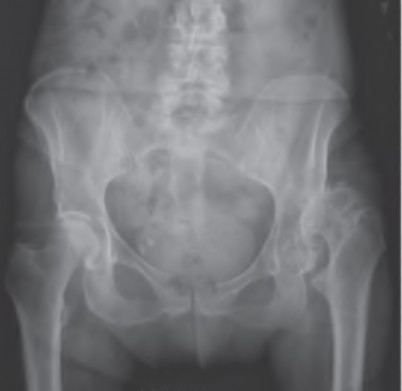

A 75-year-old man underwent total hip arthroplasty 10 years ago. He now reports mild groin pain which has been increasing lately. What is the most likely explanation for the finding in Figure A indicated with the arrows?

Osteolysis of the pelvis is a common complication associated with total hip arthroplasty. Osteolysis affects sockets with and without cement, and has been attributed to the biologic reaction to wear debris. With well-fixed cementless sockets, an expansile pattern of osteolysis is usually seen.

The radiographic appearance has a radiolucent area that starts at the implant-bone interface and expands into the cancellous bone away from the implant.

This pattern of osteolysis can be explained with the concept of effective joint space. This concept states that joint fluid and wear particles will flow according to pressure gradients and follow the path of least resistance.

The Level 5 review article by Chiang discusses osteolysis in further depth.